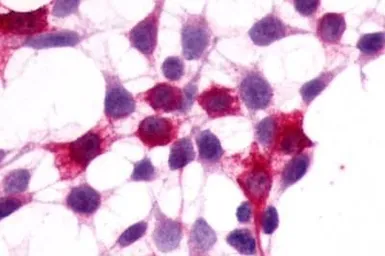

XPR1 antibody

Cat. No. GTX13290

ApplicationsICC/IF IHC-P